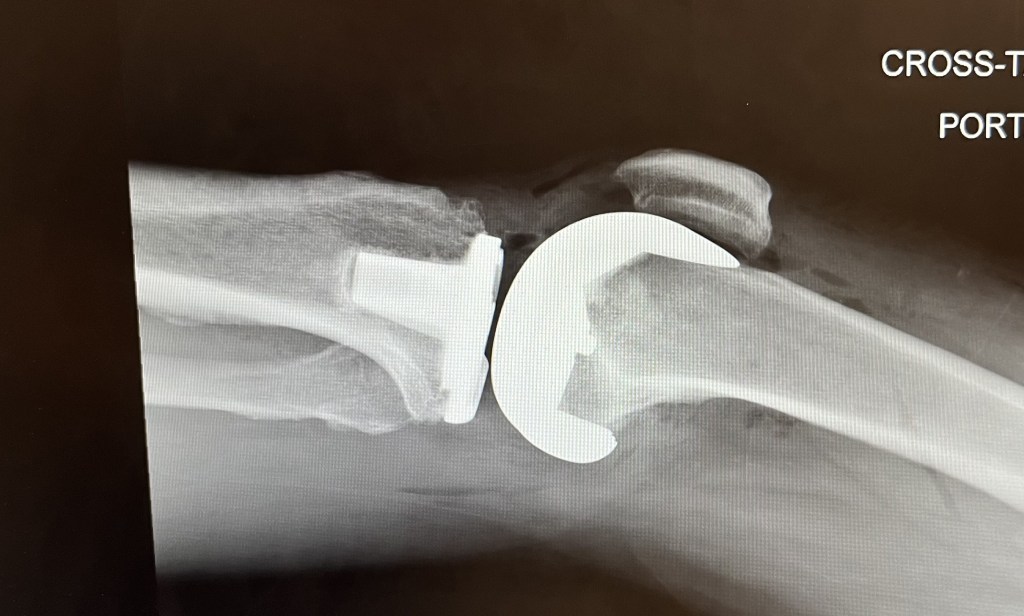

I mentioned in my last post–way back in April–that I had a full left knee replacement on April 5th. Recovery was much more difficult than I expected. The first two weeks were tough and I was in a lot of pain. After three weeks I was able to start working from home, and about that time I got back to the YMCA and was lifting weight to supplement physical therapy. PT went well and after six or seven weeks I was even able to jog a little bit.

Below. The doc worked quite the kitbash job. Guess which parts are Titanium.